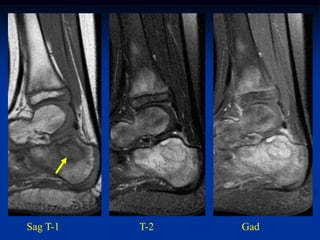

Case #444.1                  Multifocal osteomyelitis

EG pseudotumor

5 year old male with pain

in heel and knee for 6 mos

Sag T-1   T-2   Gad

Cor T-1        Sag T-2

Axial T-2